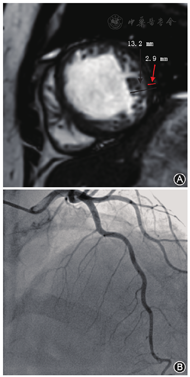

两组患者冠状动脉LAD管腔均未见狭窄,其中DCM 35例,LVEF为24.1%±8.7%,心肌局部肌小梁稍增多(图1A),年龄(53.9±10.8)岁,男性31例(88.6%),心肌过度小梁化26例(74.3%,26/35),其中5例受累节段大于3个,间隔支稀疏(图1B),平均间隔支支数为3.5支,28例LAD慢血流;LVNC 17例,LVEF为32.3%±16.1%,左心室弥漫性海绵样心肌(图2A),其中8例受累节段大于4个,平均年龄(58.4±10.1)岁,男性9例(52.9%),间隔支显影良好(图2B),平均间隔支支数为6.5支,2例表现为LAD慢血流。两组LVEF差异有统计学意义(t=2.386, P=0.021),LVNC组LVEF明显高于DCM组;两组间慢血流差异有统计学意义(t=8.423,P<0.000 1),DCM组LAD血流明显慢于LVNC组;经秩和检验,两组间隔支数差异有统计学意义(P<0.05),且LVNC组间隔支支数为DCM间隔支支数的1.9倍。

心肌慢血流现象其实并不少见,在疑似冠心病患者人群中,大约有7%的患者心外膜下冠状动脉正常,但存在慢血流现象[11],主要原因归因于心肌微循环功能障碍[12,13,14]。研究表明,DCM常伴随心肌弥漫性炎性细胞浸润[15,16],包括左心室间壁心肌的炎性细胞浸润和反复损伤修复累及微小血管,从而导致间隔支血管稀疏,而LVNC主要累及中部、心尖部左心室侧壁、前壁、下壁,很少累及室间隔,因此,间隔支受累不明显。本次研究进一步证实,DCM患者间隔支稀疏,且LAD血流表现慢血流有28例,约占80.0%;而LVNC间隔支显影良好,LAD慢血流2例,占11.8%,两组间慢血流差异有统计学意义(P<0.000 1)。可见,DCM患者心肌炎性细胞浸润的同时也累及心肌微小血管,导致微小血管的闭塞。因此,是否具备慢血流很可能是鉴别两种疾病的一个重要证据。另外,本次研究中,通过对间隔支的统计还发现,LVNC患者平均间隔支支数为6.5支,而DCM平均间隔支支数为3.5支,两组差异有统计学意义(P<0.05),且前者是后者的1.9倍。因此,通过对LAD心肌血流及间隔支分布情况的评估,对疾病的鉴别诊断可能起到积极作用。